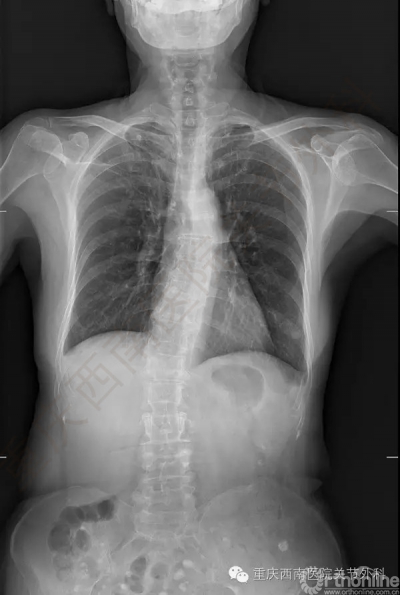

1996年的车祸导致她左侧股骨骨折形成严重的畸形愈合,股骨前后错开,髓腔封闭,类似“双截棍”,脊柱固定侧弯(图3)。